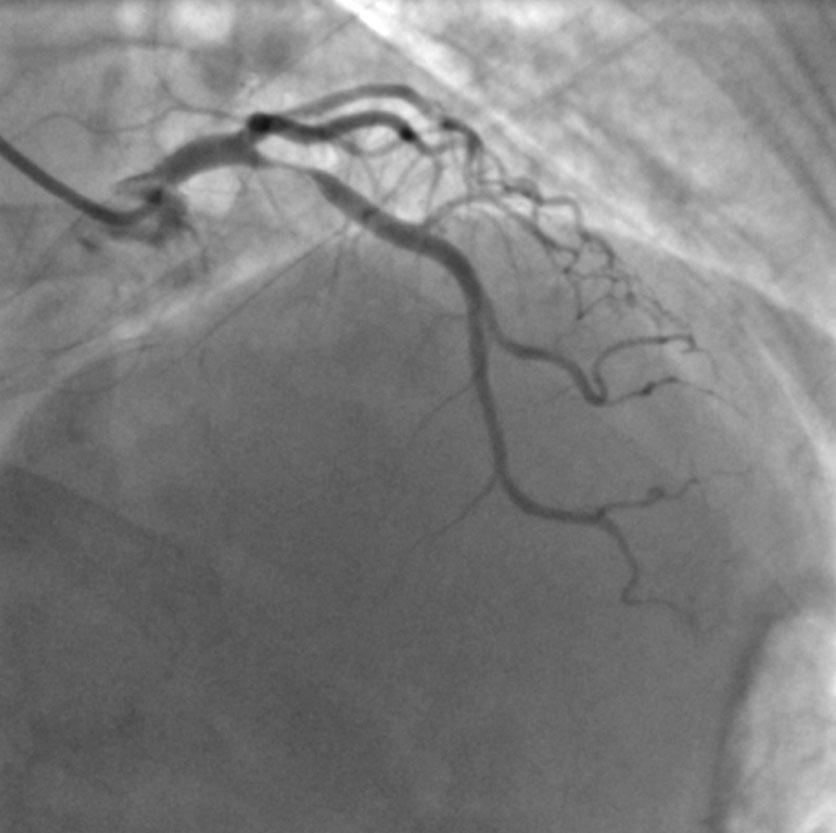

Double-LAD-Surgery

Double LAD Surgery